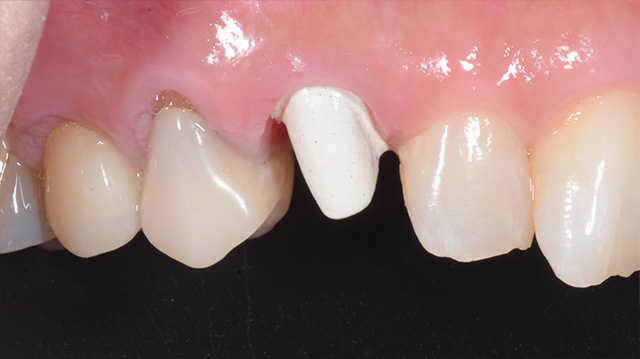

| 年代・性別 | 40代 男性 |

|---|---|

| 主訴 | 前歯の被せ物が取れた |

| 治療回数 | 3回 |

| 治療期間 | 約1ヶ月 |

| 費用 | 仮歯 5,500円 ジルコニアクラウン 176,000円 |